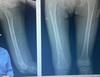

Fratura completa